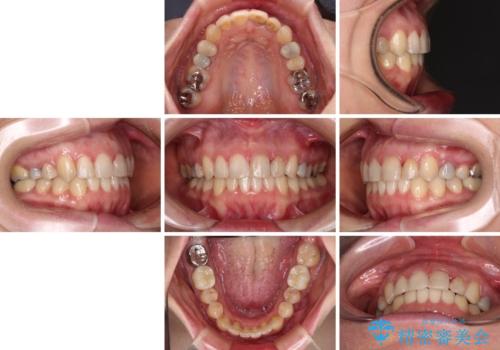

【モニター】前歯のデコボコと奥歯の虫歯 インビザライン治療と奥歯のセラミック治療

- 前歯のデコボコと奥歯の虫歯を気にして来院された患者様です。

主に下顎歯列全体の後方移動とIPR(歯と歯の間を削る)によってデコボコが解消するように設計し、インビザラインにより治療を行うこととしました。

矯正治療後半に下顎左右奥歯をセラミッククラウンにて補綴し、その後インビザラインによる歯列の仕上げを行うこととしました。

下顎前歯の叢生が速やかに改善されたため、1年3か月で治療を終えることができました。

下顎前歯は後戻りを起こしやすいため、舌側を細いワイヤーで固定することで後戻り対策を行っています。